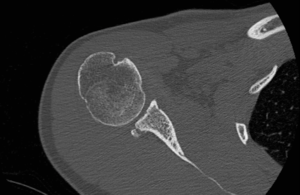

Computed Tomography (CT) Scan

Computed tomography (CT) scans also help the physicians to analyze the bony morphology of the shoulder joint. Before operative management, it is effectively imperative to assess for abnormalities in glenoid version (mean, 4.9 degrees in normal shoulders)[20] according to the Friedman technique,[21] posterior glenoid rim fractures or bone loss, and reverse Malgaigne (Hill-Sachs) lesions. These factors help determining the treatment strategies.